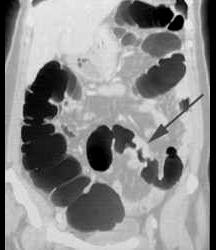

男,55岁,左下腹胀痛、并可触及包块,结合图像,应诊断为 ( )A、肠结核B、慢性溃疡性结肠炎C、结肠癌D、结肠腺瘤E、结肠crohn病

问题 男,55岁,左下腹胀痛、并可触及包块,结合图像,应诊断为 ( )

选项 A、肠结核 B、慢性溃疡性结肠炎 C、结肠癌 D、结肠腺瘤 E、结肠crohn病

答案 C